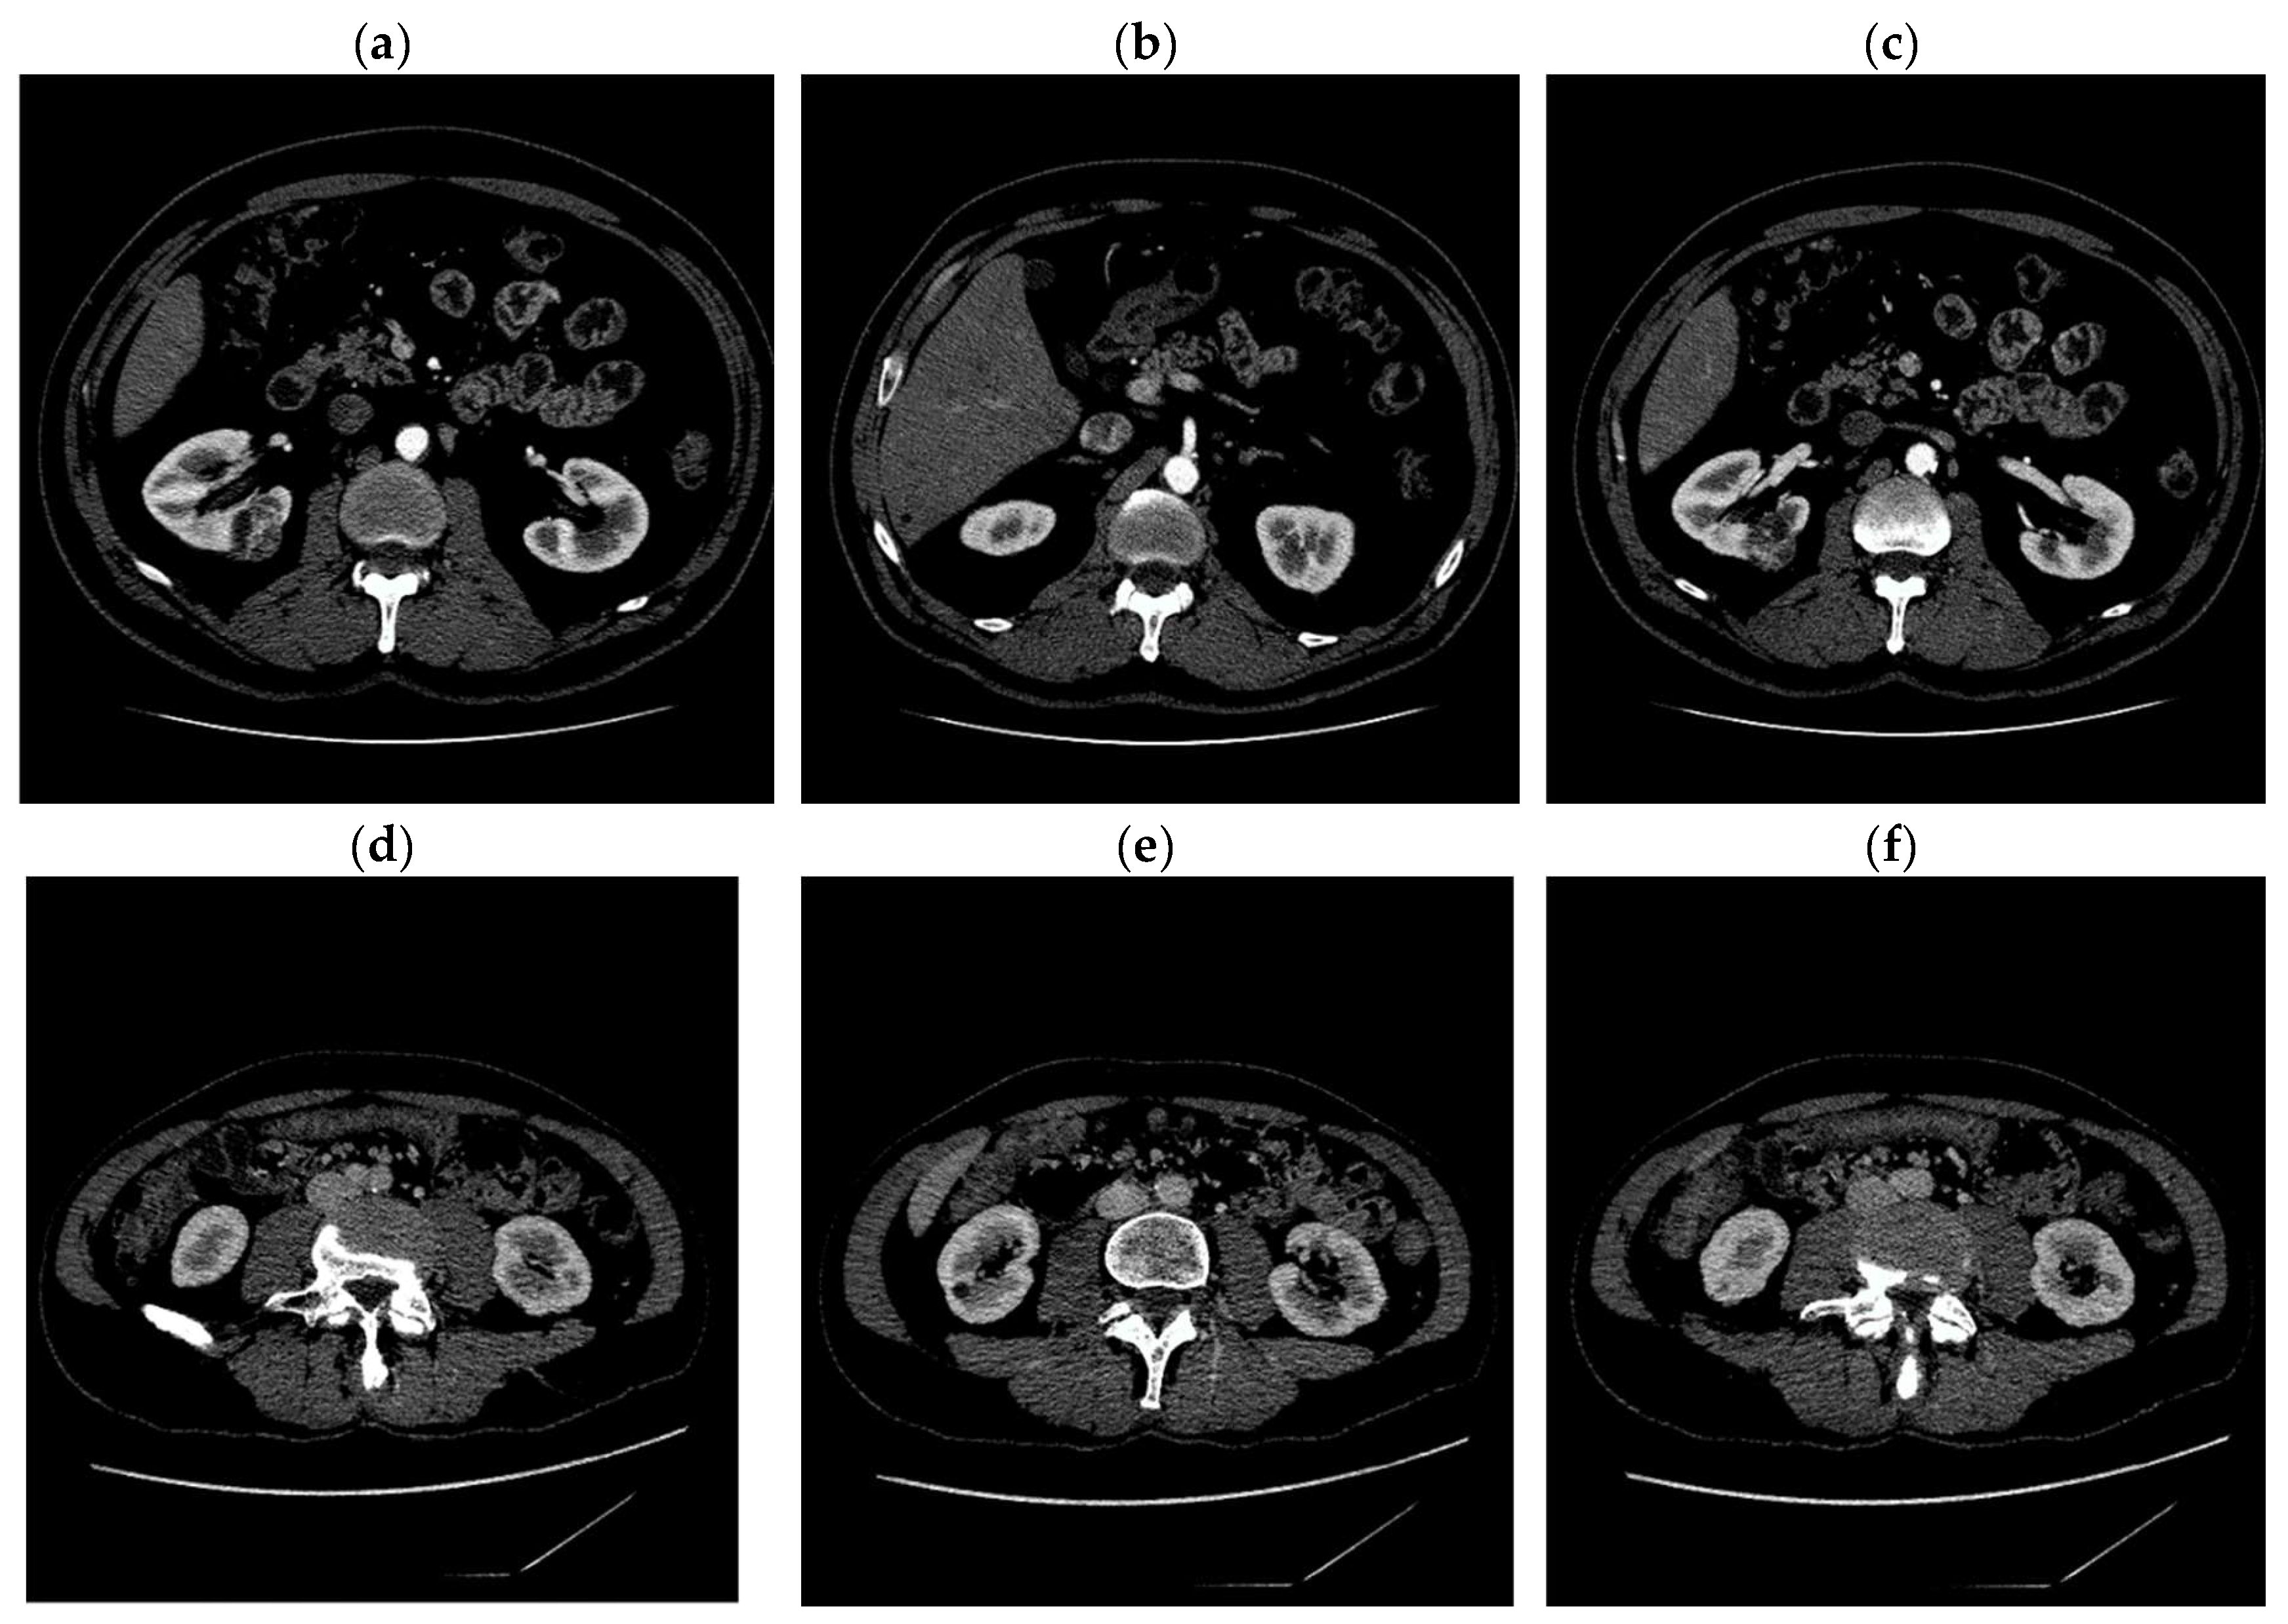

Digital images obtained as a result of computed tomography, used in our experiments, have the dimensions of 512 × 512 pixels. Exemplary CT images are shown in Figure 1.

Figure 1. The figure shows six different slices obtained from a computed tomography (CT) scan after contrast media application. In examples a and b, an infiltration of the neoplastic type is visible. The shape and size of the kidneys vary considerably. Examples (ac) come from the same patient, the same examples (df) show the same kidney but on different sections.